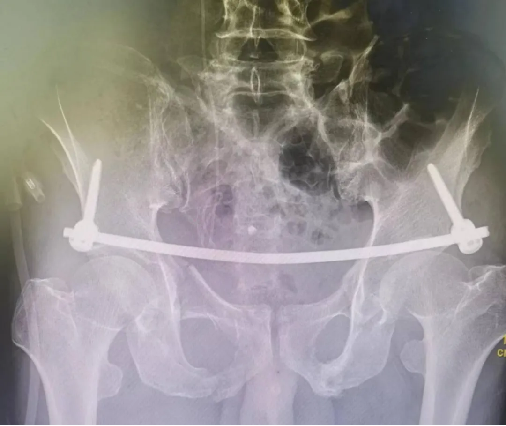

患者黄某,因车祸外伤导致全身多处疼痛入院,入院即因失血性休克于ICU监护,完善检查显示双侧耻骨粉碎性骨折、右侧髂骨多处骨折、右骶髂关节脱位,提示骨盆前-后环均不稳定。

对于此种前后环均严重失稳的复杂骨盆骨折的治疗,保守治疗不仅需长期卧床,易导致褥疮、肺部感染、泌尿系感染及深静脉血栓风险,同时势必影响后期功能恢复,严重降低患者未来生活质量。传统开放术式手术切口大、手术时间长,手术难度极大,同时存在盆腔内血管神经及膀胱的医源性损伤风险,以往,遇到此种严重病情只能依赖上级医院专家来院手术指导,但基于近期成功开展的骨盆微创治疗的经验支持,外一科董明主任反复研究患者病情及影像,充分考虑手术创伤与风险后,决定开展骨盆骨折有限切开复位内固定术。

经充分术前准备,由董明主任、余策略主治医师、叶强医师为患者在全麻下仅用不到2小时便成功完成了手术,术中出血量少,术后第二天患者就可以床上坐起及翻身,功能恢复良好。